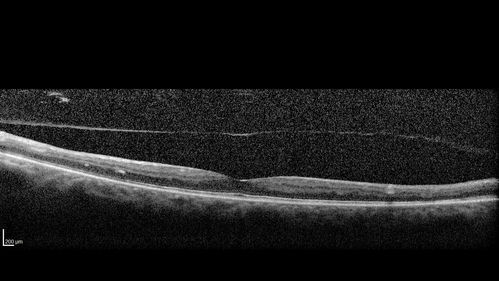

57 year old diabetic man with vision loss in the left eye for several months.  He has DME in the left eye and VH in the left eye and PDR in both eyes.  He has been started in the left eye on Anti-VEGF therapy. VA on presentation was 20/25 OD and 20/200 OS